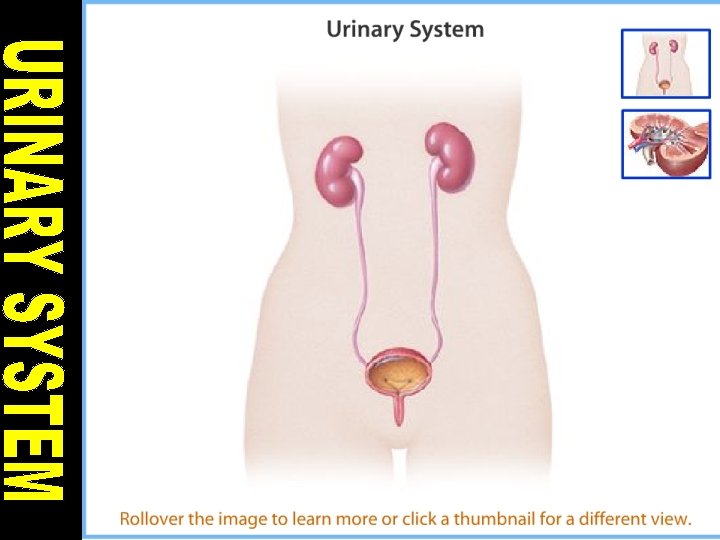

PARTS OF HUMAN EXCRETORY SYSTEM 1. Kidneys 2. Ureter 3. Urinary bladder 4. Urethra

KIDNEY • Kidneys are bean shaped organs that filtere 180 lt. blood in a day. • Blood is come into kidney by renal artery. • Filtered blood leaves from kidney by renal vein.

FUNCTIONS OF KIDNEY 1. They remove wastes of cellular metabolism from the blood. 2. They control concentration of various substances found in the body fluid.

STRUCTURE OF KIDNEY 1. Cortex: It contains glomerulus and Bowman’s capsules. 2. Renal Capsule: It surrounds and protects the kidneys.

3. Medulla: It is located under the cortex and has malphigian pyramids. Malphigian pyramids contains urine collecting canal and loop of henle. 4. Pelvis: It is innermost part of kidney. The urine is collected in pelvis.